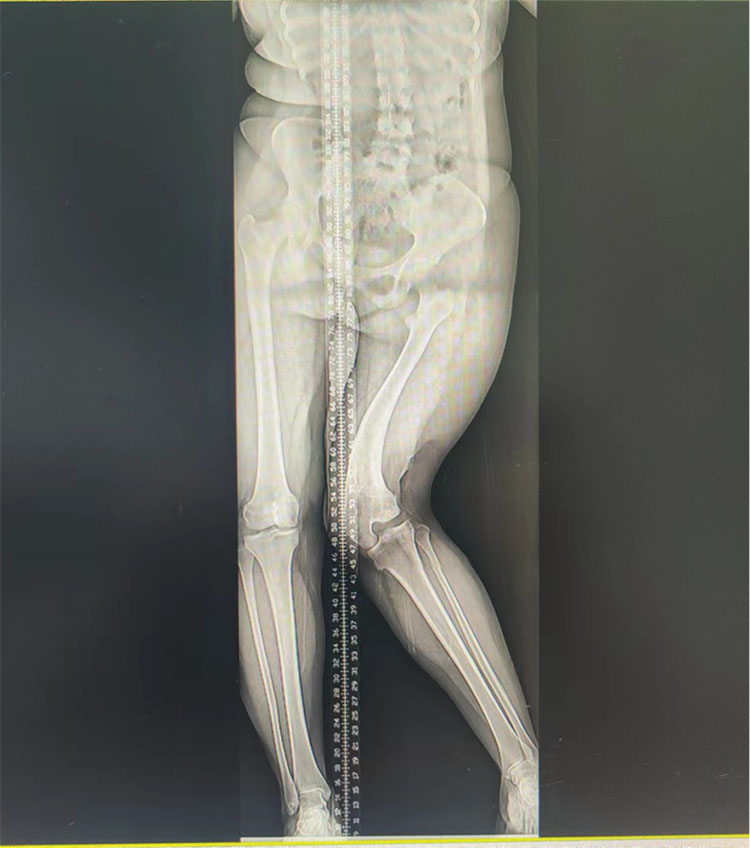

玉林市中西医结合骨科矫形骨科治疗过一位特殊的老病号—封小妹。该患者年仅20岁,但已经多次和医院打交道。不过与以往不同的是,这次患者是面带笑容来住院的,因为困扰多年的“剪刀腿”问题,终于要彻底解决了。

时间回溯到2005年,那时候封小妹才5岁,因玩耍不小心跌倒,摔断了左大腿骨,在当地医院行手术治疗。因受伤时损伤了股骨远端的骨骺线(生长发育线),术后不幸出现了严重的后遗症,骨折端畸形愈合,左大腿逐渐出现弯曲畸形。此后多年间,封小妹的家人带着她到全国各地多家医院求医,当时的接诊医师了解病情后,都直摇头,纷纷表示这么严重的畸形就算治疗,效果也不好。一次又一次的失望,封小妹和她的家人们逐渐产生放弃治疗的念头。

患者术前外观图和DR片